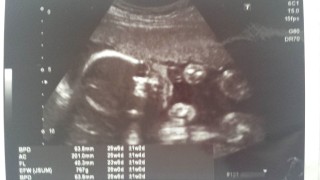

写真:25w5d:ゆりさん

初めての妊婦 やっと4Dもらえた^o^ 大きさは893g順調。 男の子と確定^_^ パパ似かなー^^